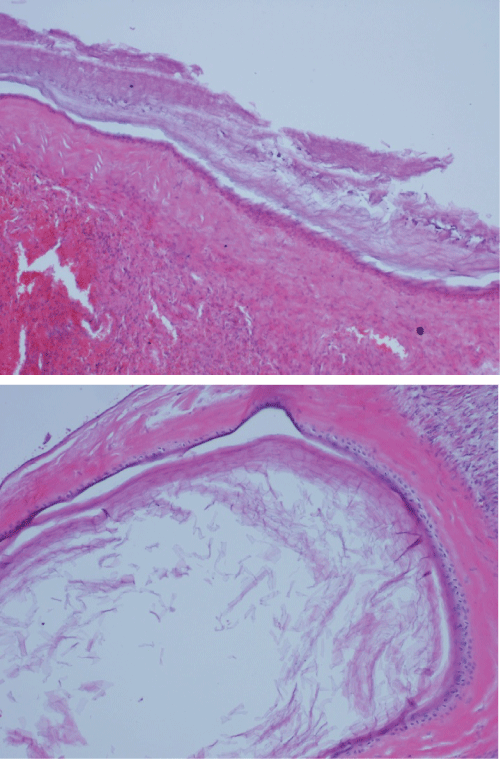

Figure 2,3: Dermoid cyst of the same ovary with squamous epithelium with keratinization (H&E, x100)

The specimen was examined by light microscopy with hematoxylin-eosin stain. Microscopic examination of the right ovary revealed three tumor types: mucinous cystadenoma corresponded to the wall of the two cysts; mature cystic teratoma produced the skin and subcutaneous tissue, including sebaceous glands and hair containing mass.